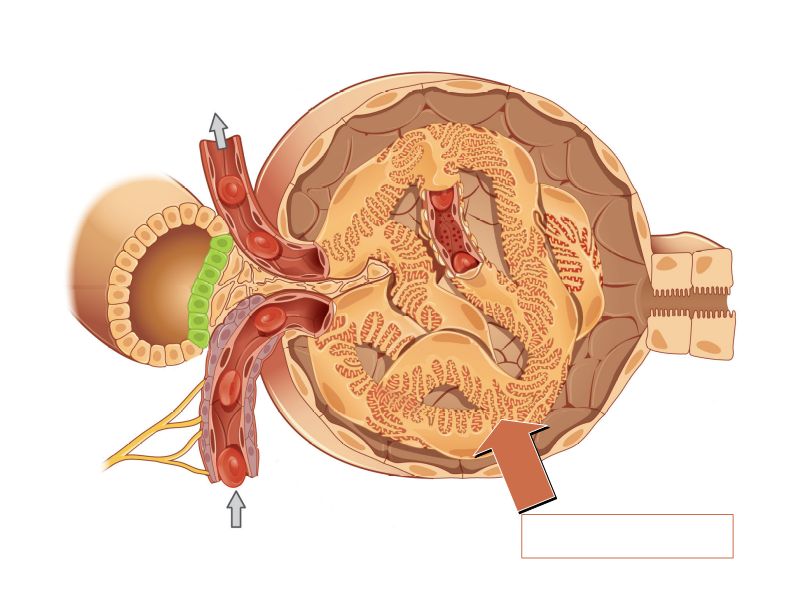

Renal corpuscle

- Tuft of capillaries

- grow into

- Blind end of nephron

- Two sides

- Vascular pole

- Tubular pole

Blood flow

- Efferent arteriole

- Smooth muscle in media

- Capillaries

- Fenestrated

- Afferent arteriole

- Smooth muscle in media

Capillaries

- Supported by

- Mesangial cells

- Mesangial matrix

- Phagocytic

- Maintain basement membrane

- Remove macromolecular deposits

Mesangial cells

- Around capillary loops at vascular pole

- Phagocytic

- Maintain basement membrane

- Remove macromolecular deposits

Podocytes

- Visceral layer of epithelium

- Protrude into capsular space

- Attached to basement membrane

- Long cytoplasmic extensions

- Primary processes

- Secondary processes

- Podocyte feet

- Tightly spaced

- Filtration slits 20 - 30 nm wide